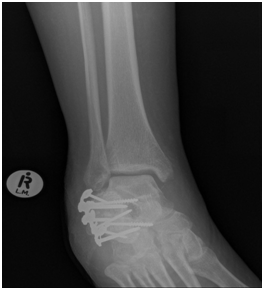

Radiological assessment shows

L3 unstable spine fracture, Right intara-articular calcaneal fracture of joint depression type, Saunder’s III AC3,4(Figure 1 & 2).

Figure 1 CT Calcaneus showing multi fragmentery intra articular fracture.

Figure 2 CT Calcaneus showing joint depression and intra articular extension.